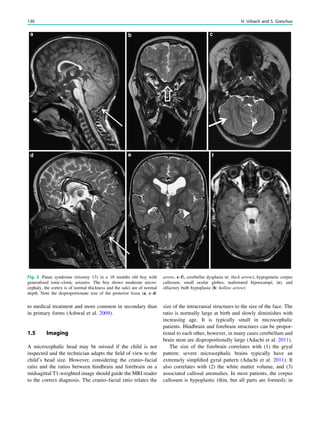

Fig. 1 Digital photogram of the brain surface before placement of a

subdural 8 9 8 grid. A second photogram was taken after grid

placement and digitally replaced by a schematic drawing detailing the

results of electrical stimulations and ictal/ intraictal EEG activity. Blue

grid contacts represent the eloquent zone, which is the motor cortex in

this case. The black area represents the epileptogenic lesion, defined

as the radiographic lesion that causes the seizures. The yellow area is

the seizure onset zone, defined as the area from which the clinical

seizures are generated. The seizure onset zone is often, but not

necessarily, congruent with the epileptogenic zone, defined as the

cortex area indispensable for the generation of seizures